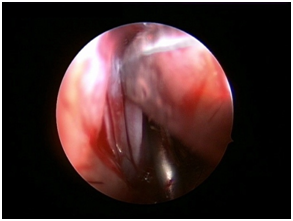

Nasal Endoscopy is done to assess the septal deviation and spurs (Figure 1) ( Figure 2). Septal infiltration is carried out with a solution of 2% Xylocaine with 1: 100,000 adrenaline in the sub-mucosal plane. It is given with a single prick at the inferior most part of the nasal septum at the junction of the septum with the floor of the nasal cavity anterior to the mucocutaneous junction. The infiltration is given at the same point on both the sides (Figure 3). The incision is always given on the deviated side. It is given anterior to the mucocutaneous junction because the skin present at that place is thick and chance of a tear of the flap is less (Figure 4). The mucoperichondrial flap is raised on the deviated side with a Freer’s elevator strictly under vision. The flap is not to be raised beyond the deviated part because the part of the septum posterior to the deviation is not under direct vision (Figure 5) (Figure 6). The caudal end of the septum is then palpated and an incision is given on the cartilage 1cm behind the columella. This 1cm of the cartilage is saved to prevent post operative tip deformities (Figure 7). The cartilage is sliced and the opposite side is entered, the mucoperichondrial flap of the opposite side is then elevated with a Freer’s elevator. A cut is given in the septal cartilage as high as possible. A septal window is created and a Ballenger’s swivel knife is taken and lodged in the place where the cartilage was cut. Creation of a septal window thus increases the area of exposure (Figure 8) (Figure 9). The flap on the non-deviated side is elevated till the bony-cartilaginous junction.

After reaching the bony-cartilaginous junction, the flap is elevated downwards towards the floor. The elevation is done from posterior to anterior direction. This makes the flap on the non-deviated side safe. The Freer’s elevator is placed in the bony-cartilaginous junction and the inferior strip of cartilage is sliced off from the maxillary crest from posterior to anterior direction. The strip of cartilage is gently swung out. In case of any spur, bony or cartilaginous, the flap over the spur is never elevated directly. The cartilage/bone above the spur is cut at multiple levels and the pieces are removed with the help of a Blakesley’s forceps. The Freer’s elevator is placed between the spur and the flap and the spur is gently pushed to the non-deviated side and is removed with the Blakesley’s forceps (Figure 10). In case of any deviation or spur from the maxillary crest, it is chiseled out. The direction of the chisel is always towards the maxillary crest only. The flaps are repositioned and a diagnostic nasal endoscopy is done to assess the patency of the nasal cavities. Nasal packing is done using commercially available sponge packs made from cross-linked polyvinyl alcohol (Merocel®) using a Thudicum’s nasal speculum, in order to prevent the reflection of the flap at the incision site. The immediate post-operative management includes intravenous antibiotics and analgesics. Nasal pack is removed on the second day after surgery and patients are advised oral antibiotics, analgesics, anti-histaminics and decongestant nasal drops for one week. Patient is advised saline nasal douching for a week and discharged on the second day after surgery with a prescription of oral antibiotics, anti-histaminics and decongestant nasal drops for one week. Saline nasal drops are given for two weeks after surgery.

Figure 7 Cartilage incision.

Figure 8 Ballenger’s knife- septal window.

Figure 9 Exposure after septal window.